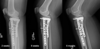

What is shown in these radiographs?

progression of primary bone union